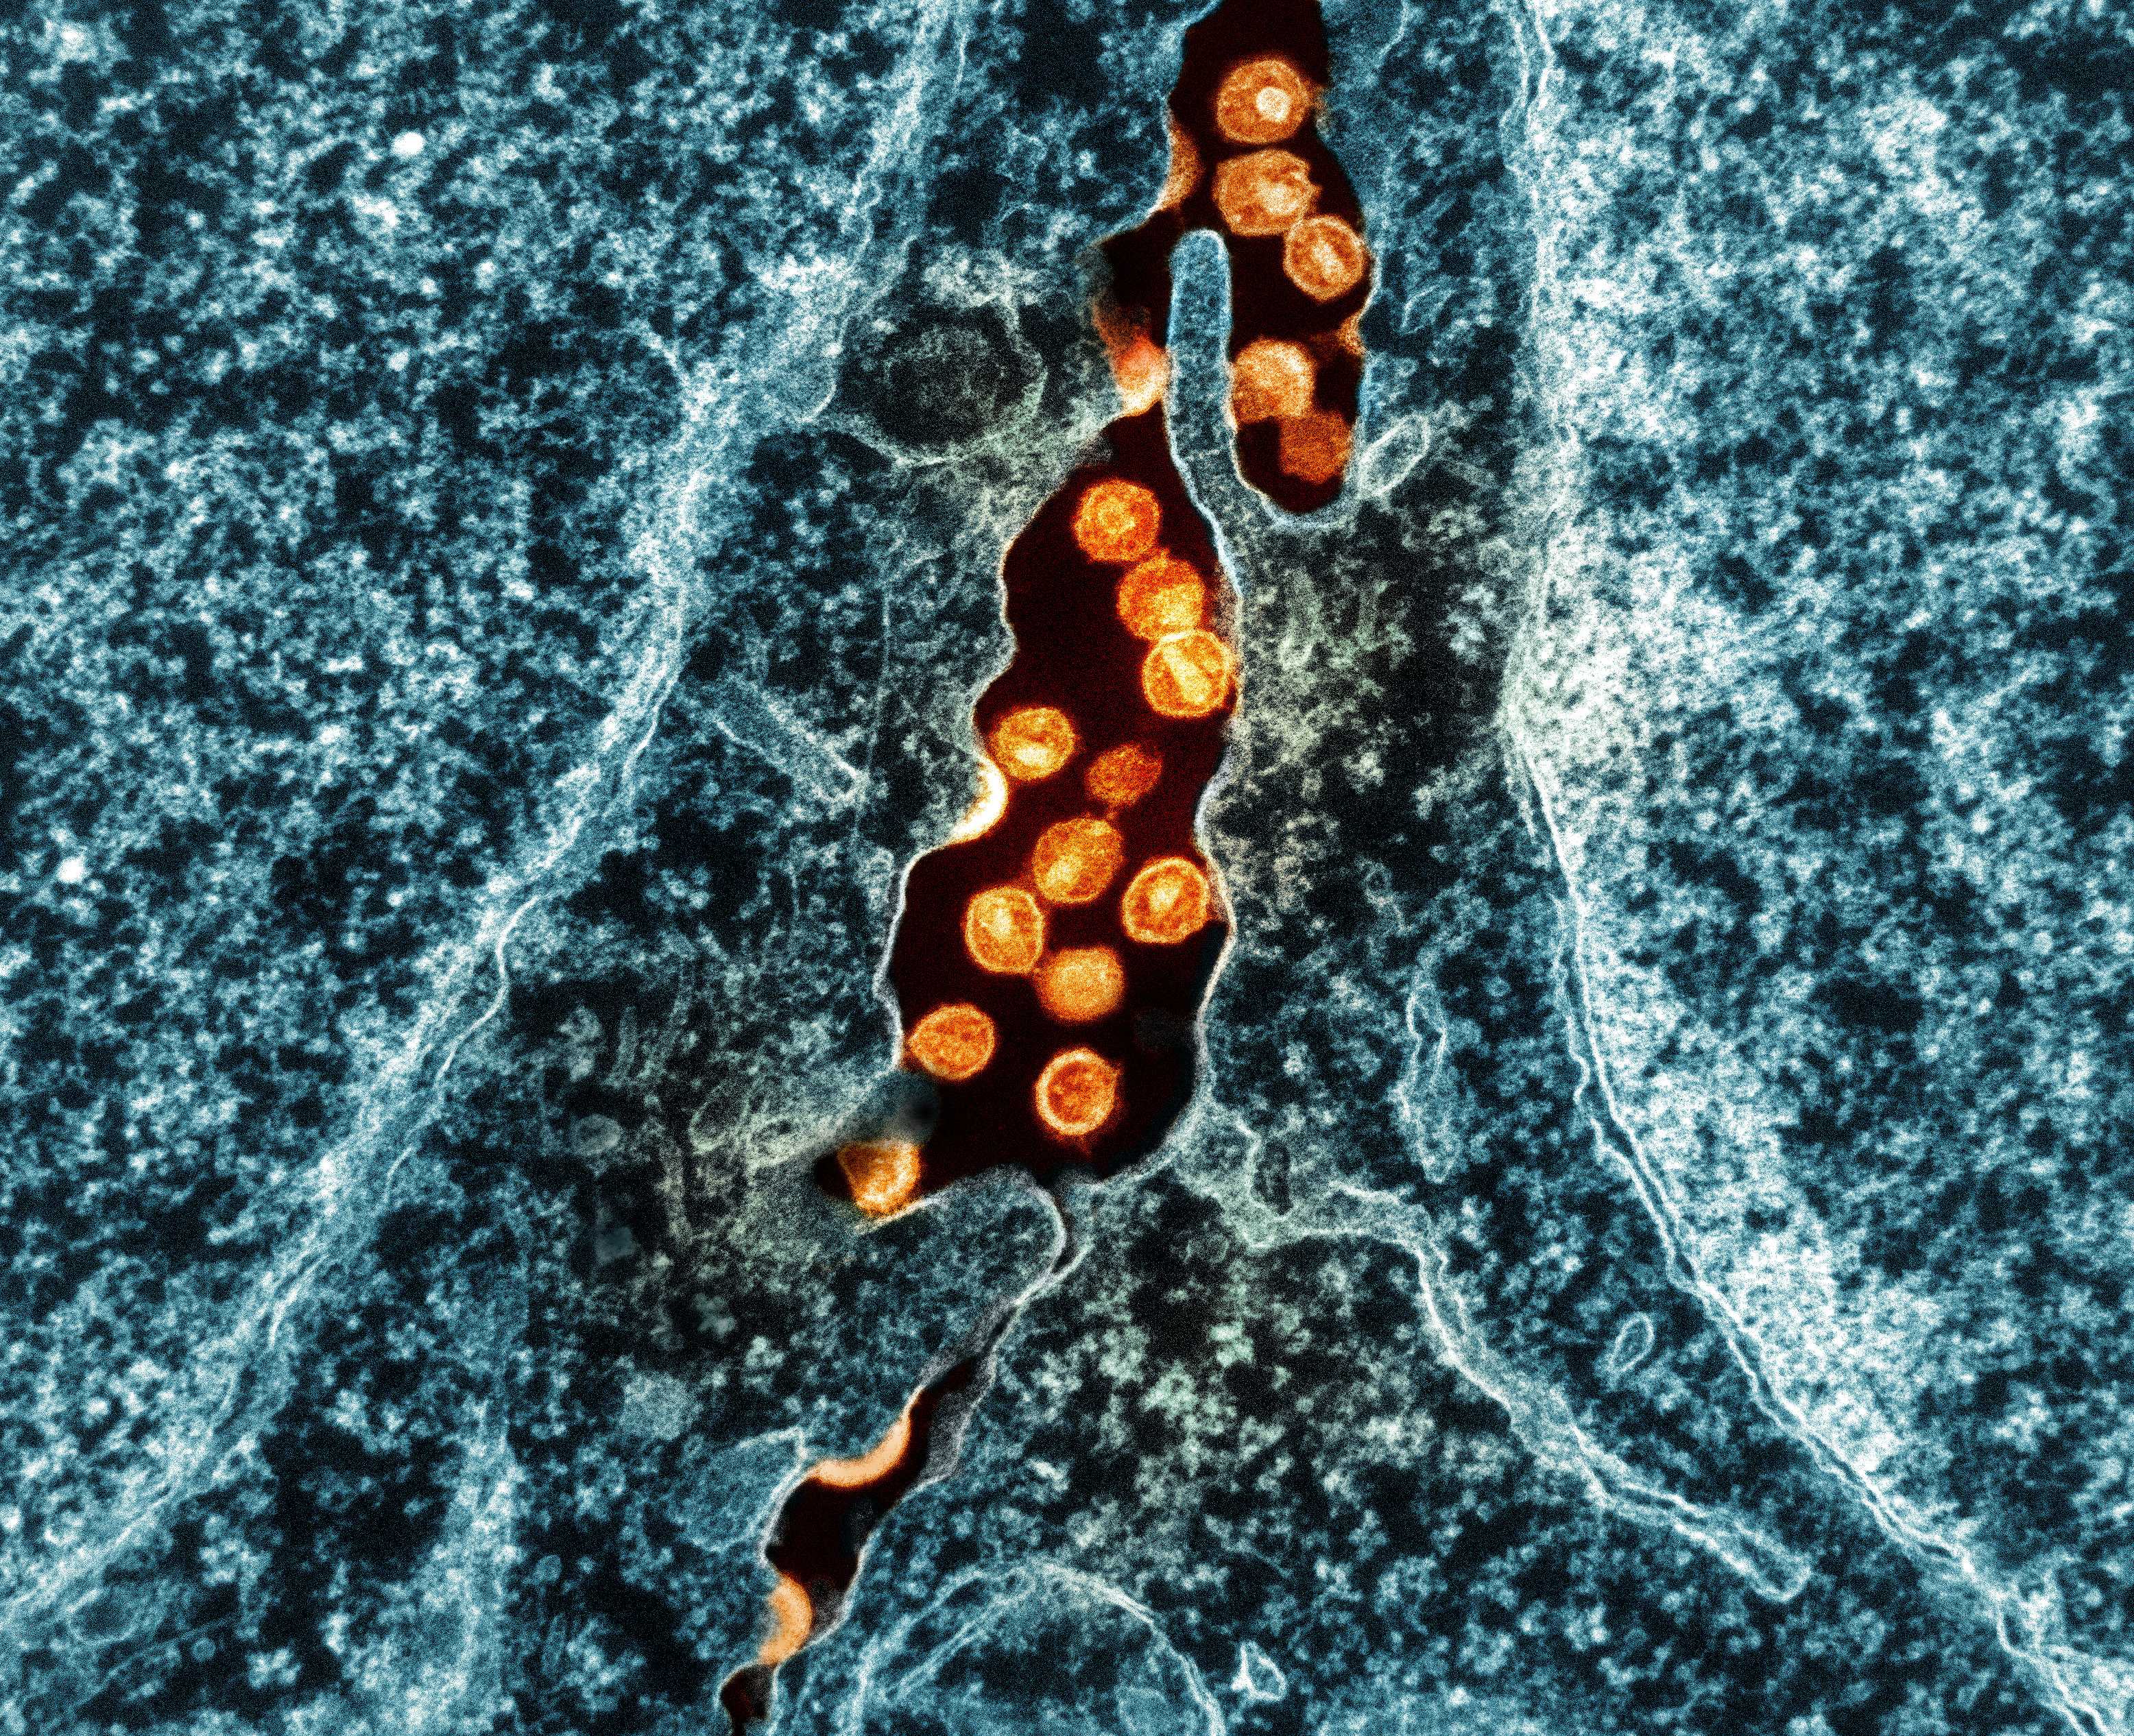

Документированных случаев избавления от ВИЧ в мире немного, и все они связаны с пересадкой больным стволовых клеток крови от доноров, несущих мутацию в гене CCR5. Именно он кодирует белок, который вирус иммунодефицита человека использует для проникновения в иммунные клетки. Мутация CCR5-Δ32 приводит к образованию дефектного белка, к которому вирус присоединиться не может, поэтому теряет способность к заражению.